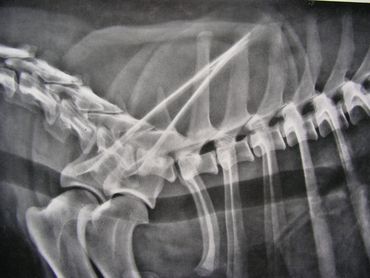

The spinal column is made up of four major vertebral regions: cervical (neck), thoracic (mid back), lumbar (low back) and sacral (pelvic). Dogs have seven cervical, thirteen thoracic, seven lumbar and three sacral vertebrae. There are also variable numbers of coccygeal or tail vertebrae. Intervertebral disks are located between the vertebral bodies starting at the second and third cervical vertebrae (C2-3) and extending to the seventh lumbar and first sacral vertebrae (L7-S1). The three sacral vertebrae are fused and therefore do not have disks. Intervertebral disks are present between the coccygeal vertebra as well, but are of little clinical significance.

The canine spinal anatomy is very similar to us humans, with the exception of 1 additional thoracic vertebra and 2 additional lumbar vertebra...